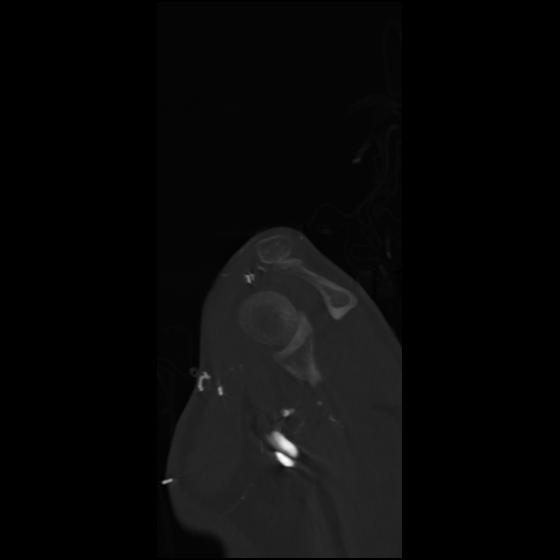

24 ANGIO,CE,Sag-MIP,5.000,ANGIO,Sag-MIP,